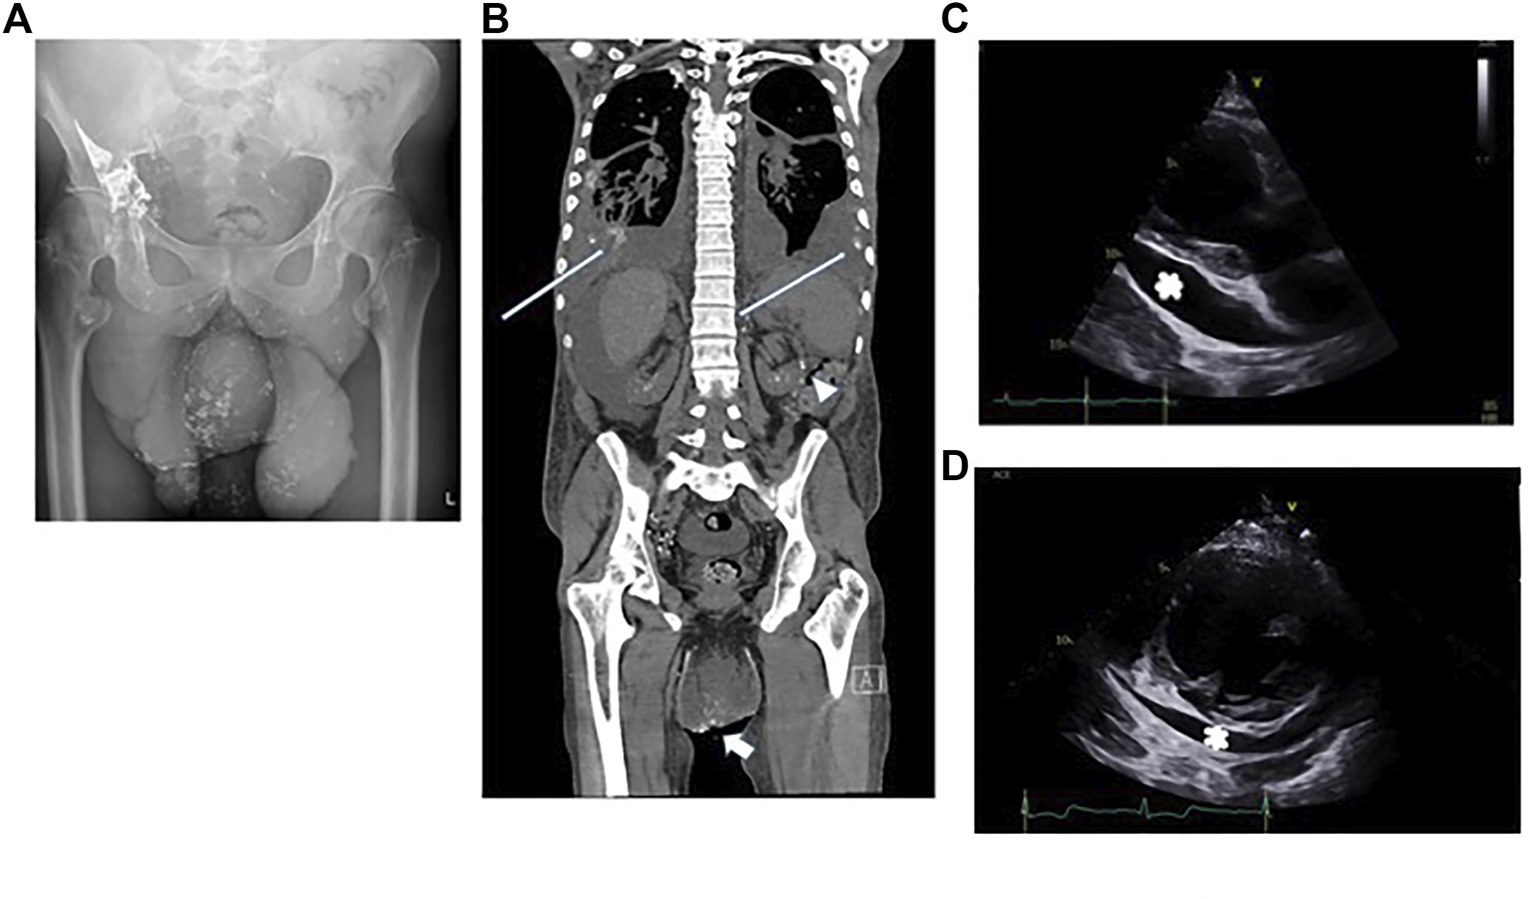

Despite trying to manage these effusions in the outpatient setting he required urgent admission to his local hospital for peritonitis. Treatment with high dose diuretics failed to control his symptoms. Large volumes of fluid were drained from his abdomen (3.5 L) and pericardium (1.8 L). Analysis of the fluids confirmed they were chylous: fluid albumin level 32 g/L (serum albumin 31 g/L) triglyceride level 5.9 mmol/L (serum triglyceride 1.06 mmol/L), cholesterol 2.1 mmol/L (serum cholesterol 2.17 mmol/L), protein 4.7 g/L and chylomicrons were present in the fluid. He underwent multiple investigations, including Intranodal Lymphangiography using Lipiodol. Only a single lymph node was identified that could be targeted in the right groin. The procedure was carried out under fluoroscopic guidance following initial ultrasound guided puncture of an inguinal lymph node, followed by injection of Lipiodol at a rate of approximately 0.5 ml/min. Once contrast was seen in the chest, the study was terminated, and a delayed x-ray was performed 2 h later. The initial study and the delayed x-ray confirmed reflux of lymphatic fluid into the penoscrotal mass (Figure 4A). A delayed non contrast CT scan performed 4 h later demonstrated leakage of contrast (lymphatic fluid) bilaterally into the pleural effusions and leakage or reflux of contrast into the small bowel mesentery (Figure 4B) but this was not felt to be amenable to surgery or embolisation.

FIGURE 4

Patient B: (A) Reflux of contrast into the penoscrotal mass from the right inguinal lymphatics. (B) Non contrast CT showing bilateral pleural effusions, ascites and the penoscrotal mass. Long white arrows show residual lipiodol leakage into the pleural effusions bilaterally. Arrowhead shows lipiodol in the small bowel mesentery. Short white arrow shows lipiodol reflux into the scrotum. (C) Echocardiogram, 2 months after pericardiocentesis -parasternal long axis view showing a large >2 cm pericardial effusion (white asterix) adjacent to the left ventricular posterior wall. (D) Echocardiogram, 4 months after commencing treatment with trametinib parasternal short axis view confirming reduction in pericardial effusion size around the left ventricle (marked with a white asterix).

The transthoracic echocardiogram 2 months after pericardiocentesis demonstrated a marked increase in the size of pericardial effusion since drainage: seen largest at 2.7 cm around the basal lateral left ventricular wall and 2.9 cm around the right atrium. All echocardiographic signs of hemodynamic compromise were noted including ∼50% trans-tricuspid respiratory Doppler variation, systolic collapse of the right atrium, diastolic collapse of the basal right ventricular free wall and a dilated and fixed inferior vena cava (Figure 4C).

The albumin level improved (29–39 g/L) reflecting an improved nutritional state. There was a total resolution of ascites within 3 months. The pericardial effusion took longer to resolve but 18 months into treatment, the fluid was considerably reduced with only small to moderate fluid (Figure 4D). Furthermore, there were no obvious echocardiographic signs of hemodynamic compromise noted.